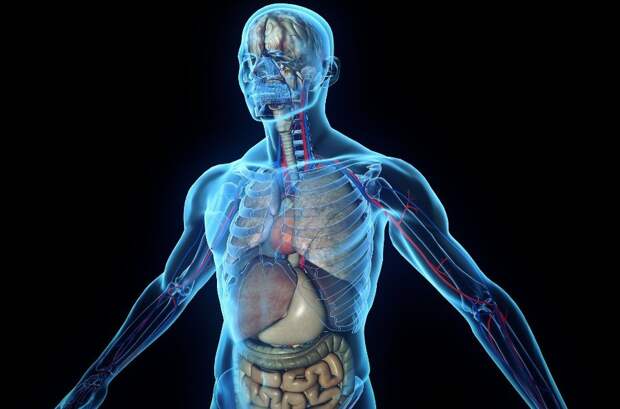

Человеческое тело — очень сложный механизм, который функционирует очень слаженно. Ежесекундно в нашем теле протекает множество процессов, некоторые из которых до сих пор ставят ученых в тупик. Далее несколько интереснейших снимков и гифок, которые помогут вам поближе познакомиться с телом человека.

7. Артерии и вены